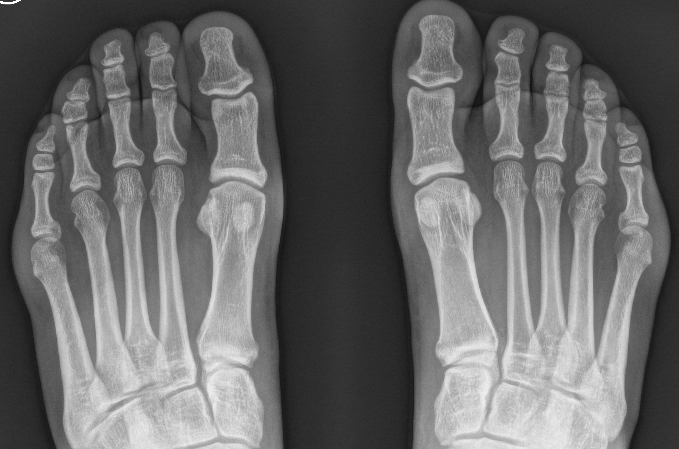

Xray

Bilateral weight bearing xrays

Proximal migration of the sesamoids associated with Grade 3 complete tear

Grade 3 plantar plate injury without proximal migration sesamoids